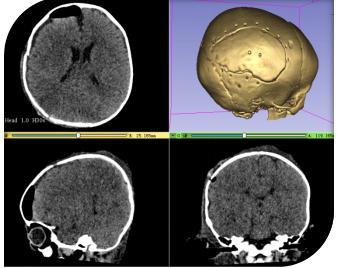

术后骨瓣还纳,为大程度减小手术切口及不影响患儿以后颅骨的生长发育,采用精准影像融合技术定位,以及可吸收颅骨锁固定骨瓣,手术顺利。术后在重症医学科严密观察患儿意识及生命体征,48 小时后患儿各项生命体征平稳,转回神经外科一病区继续治疗。

经过医护人员 2 周的专业治疗和精心护理,患儿病情恢复良好,术后复查头颅 CT显示:血肿完全清除,中线恢复居中,骨瓣回位良好,现已治愈出院。